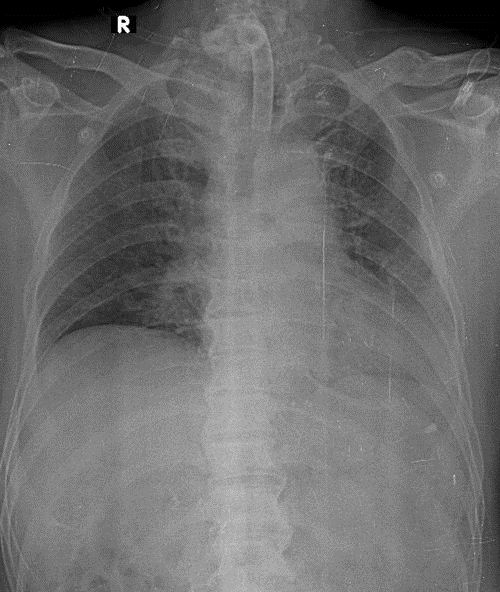

1-Đang đặt dụng cụ canul mở khí quản ra da 2-Thâm nhiểm thùy trên phổi (T) 3-Gãy 1/3 giữa xương đòn (T)